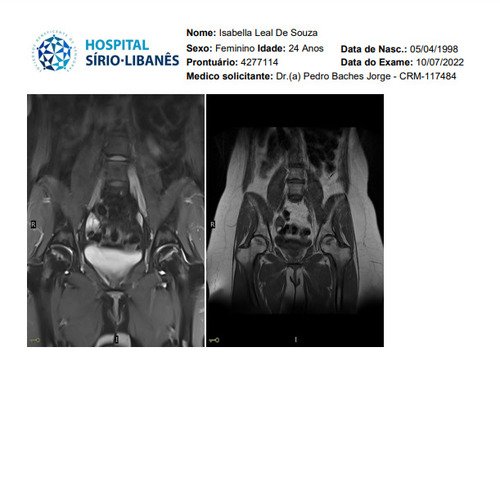

Não sei por onde começar porque e uma história longa e vou tentar resumir, fiquei meses tentando descobrir que eu tinha fibromialgia, porém eu não tenho só isso, tive edemas na coluna, problemas na lombar, e até derrame pleural eu tive, eu pago aluguel que e 1300 mais o condominio que e 450, fora que eu me planejei e não tenho familia pra apoiar entre outras coisas, quando me mudei e planejei pra poder ter o proprio ape eu não sabia que do nada iria ficar doente, em março de 2023 eu pego as chaves mas até la ta dificil, fiz emprestimo e várias outras coisas porque só a medicação de durogesic que eu uso e restiva um a caixa e 650 e o outro 300, podem pesquisar, após um procedimento na lombar cirurgico pra tentar aliviar a dor descobri uma necrose asseptica na cabeça dos dois femur, com risco de ter que colocar uma protese, até pouco tempo estava de muleta, só podia ficar sentada, e mesmo a dor e muito forte, eu ainda não sei a tal outra doença que eu tenho, já aconteceu de eu entrar na emergência e ficar na UTI, tive mais de 10 internações no hospital e não e mentira, minha maior luta e conseguir tratar essa necrose, poder voltar a praticar esportes, sei que tem gente que precisa muito mais mas eu cheguei no meu limite e to até com um aluguel atrasado, todas as coisas que eu estiver pagando eu vou colocar nota fiscal porque eu não to aqui pra fazer ninguém de trouxa, vou colocar exame, fotos de internação entre outras coisas que posso, porque tem algumas que não posso devido porque não quero imagem negativa para local de trabalho (e aonde eu trabalho eles estão me ajudando e muito), e de acordo de como for funcionando a vakinha eu vou vendo se aumento, eu só queria me livrar dessas contas sufocantes primeiro, e agora os médicos estão lutando pra descobrir a outra doença que tenho além dessa da necrose que ta me deixando muito mal e que a fibromialgia atrapalha a descobrir, sei que e chato porque já pedi ajuda 2 vezes, mas conversei com amigos e infelizmente eu não tenho outra opção a não ser pedir ajuda, vou colocar exame de tudo etc, o valor até de emprestimos que estou devendo e tudo mais, e podem me perguntar qualquer coisa que eu respondo e claro, vou postar nota fiscal pra provar que to pagando o que to mostrando, eu to no meu limite, e não e fácil, eu ficava 3 dias seguidos sem conseguir dormir e os médicos não conseguiam descobrir e ainda sigo firme no tratamento porque vou encontrar uma resposta e não posso desistir do tratamento, eu poderia fazer um textao aqui mas com poucas palavras já consigo ser direta, obrigada a quem ajuda e continua me apoiando desde o começo e pra quem não gosta e não acredita e só não ajudar, ninguém vai ficar inventando internações etc pra ficar ai pedindo dinheiro de graça pra ostentar, não gosta só não infernizar, só cada um sabe o sofrimento que ta passando na própria pele e a sua luta diária, agradeço se puder ajudar, aceito tudo que seja positivo e desejo o dobro de bom pra cada um.